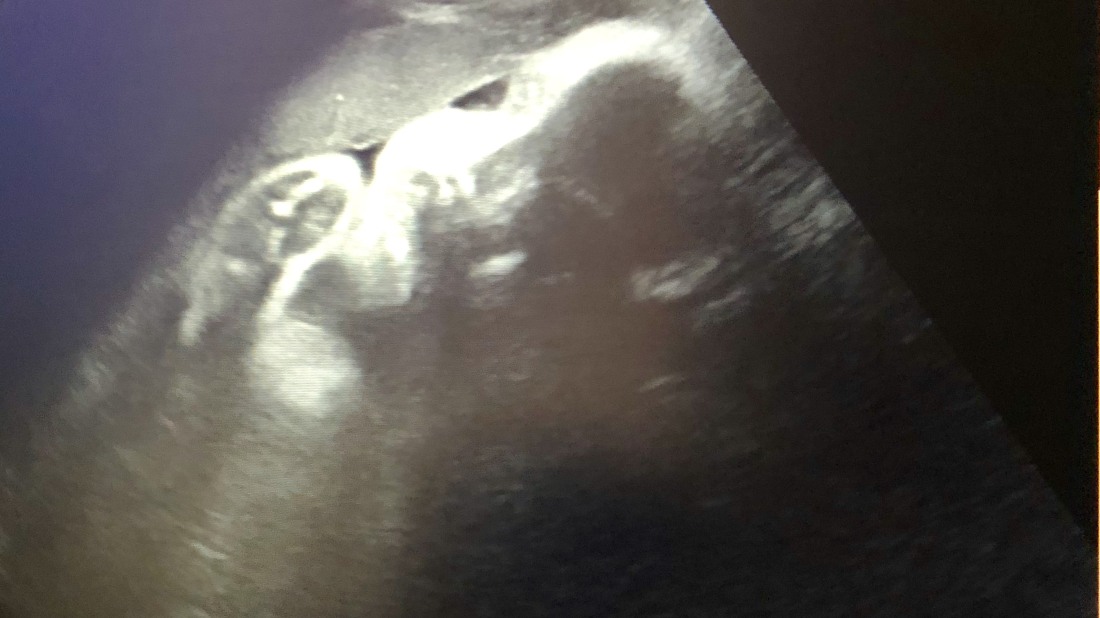

Velký ultrazvuk. Zdroj: archiv blogerky